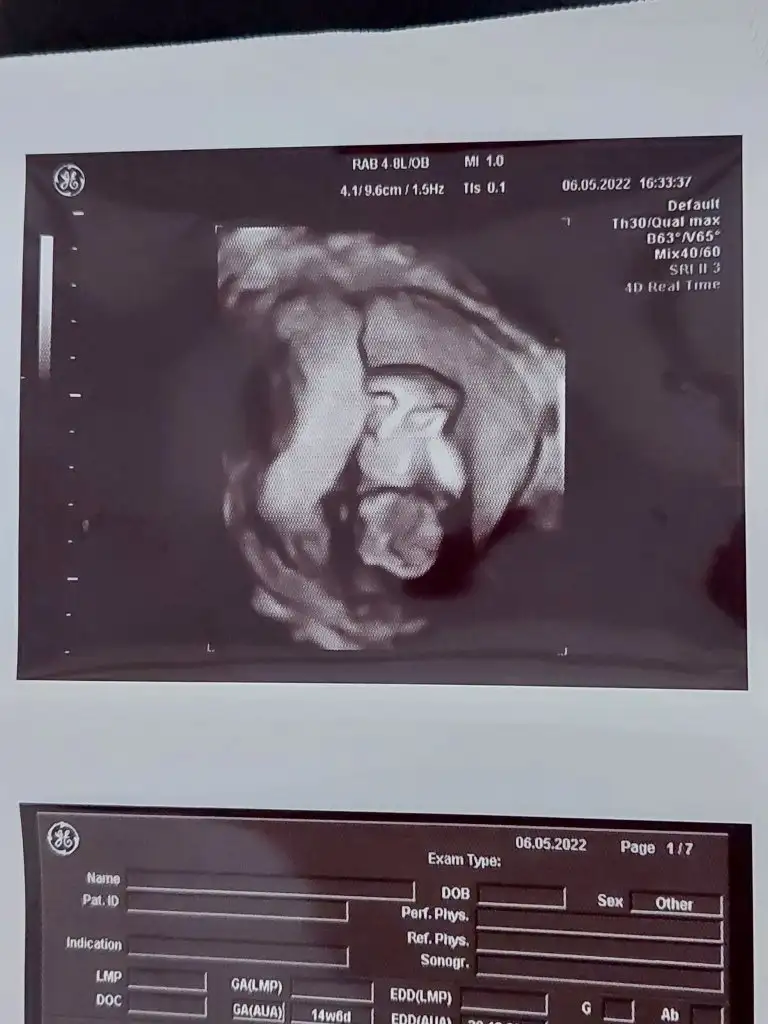

Mrb 12+6 tahmin alabilir miyim lutfen ikra meyra 🙏

Eklentiler

• IMG_20220510_114117.webp

IMG_20220510_114117.webp

14,7 KB · Görüntüleme: 98